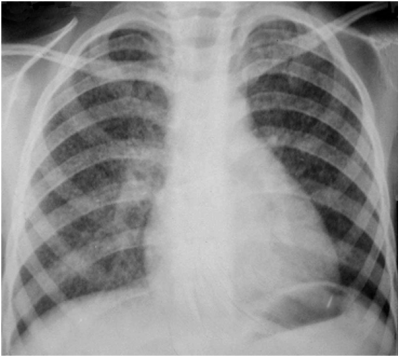

Для стадии рассасывания и уплотнения характерно постепенное исчезновение перифокальной инфильтрации в лёгочной ткани и перинодулярной инфильтрации в области корня лёгкого. Компоненты первичного комплекса в лёгком, лимфатических узлах и связующий их лимфангит можно определить более отчётливо. Лёгочный компонент обычно представлен ограниченным затемнением или фокусом средней интенсивности, лимфатические узлы - расширением и деформацией корня лёгкого. Чётко можно выявить "симптом биполярности" поражения (рис. 18-13). В дальнейшем размеры лёгочного компонента и поражённого корня лёгкого продолжают уменьшаться; постепенно в них обнаруживают признаки кальцинации. Длительность стадии рассасывания и уплотнения составляет около 6 мес.

Рис. 18-13. Стадия рассасывания первичного туберкулёзного комплекса верхней доли правого лёгкого. Обзорная прямая рентгенограмма.